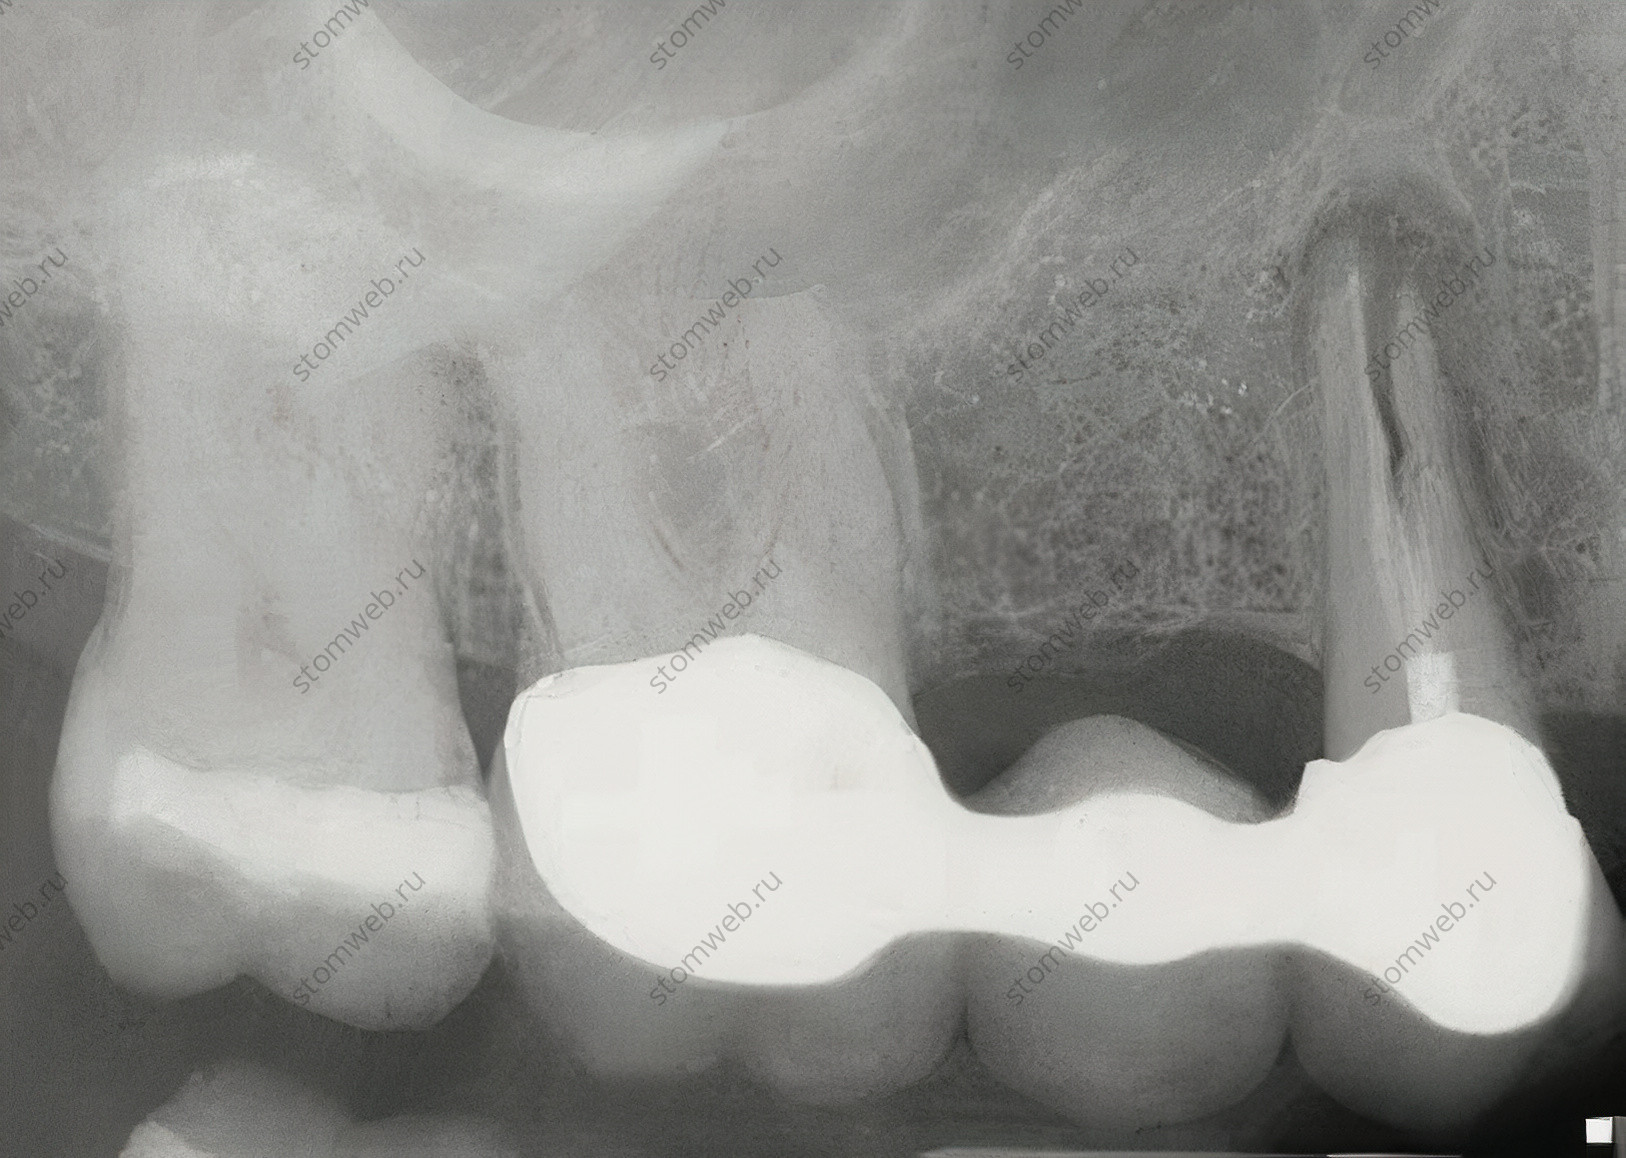

Вертикальные переломы чаще всего встречаются в эндодонтически пролеченных зубах (Рис. 2); случаи вертикальных переломов в витальных зубах были описаны, но встречались они у некоторых народов Азии со специфическими жевательными привычками. Вертикальные переломы в депульпированных зубах чаще всего появляются в апикальной части зуба и прогрессируют коронально; но иногда они появляются в пришеечной области и распространяются в длину. Диагноз обычно основывается на истории лечения (эндодонтическое лечение), рентгенологической картине и клинических проявлениях. В большинстве случаев зуб удаляется.

Рисунок 2. Рентгенограмма с показанным на ней верхнечелюстным первым премоляром с вертикальным переломом корня. Что характерно, такие переломы появляются в эндодонтически леченных зубах, и направление трещины обычно буккально-небное/язычное, хотя они и редко видны на снимках.